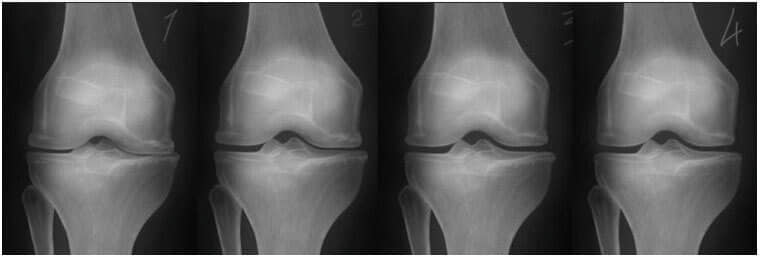

1. Eklemde beslenme eksikliği. Kıkırdak dokusu yok oluyor.

2. JointFlex kreminin 2 haftalık kullanımından sonra eklemin kıkırdak

dokusunun yenilenmesi.

3. JointFlex kremin 3 haftalık kullanımından sonra eklemin kıkırdak

4. Bir kür JointFlex kullanımından sonraki sağlıklı eklem.

- Aşağıdaki röntgen, tipik bir diz eklemi iyileşmesi sürecini göstermektedir.